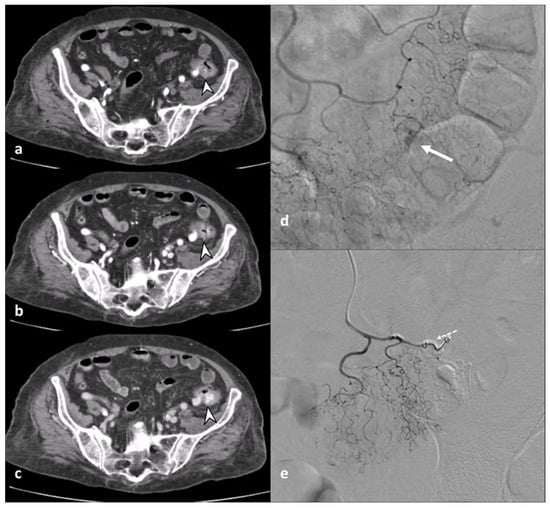

Figure 4. Axial contrast-enhanced arterial (a), portal (b), and delayed (c) CT phases show the presence of arterial active contrast extravasation within a diverticulum (arrowheads), more appreciable in the later phases of the study (b,c); this is a typical finding of active bleeding. Following DSA (d,e) reveals active extravasation of iodinated contrast medium (arrow), allowing identification of the source of the bleeding, which was then treated with coil embolization (dotted arrow in (e)).

The inflammatory process could cause engorgement of the mesenteric vessels at the involved colonic tract, which is appreciated on CT images as the “centipede” sign [18]. ACD is one of the most common causes of pylephlebitis, ascending septic thrombophlebitis, characterized by inflammation and septic thrombosis of the mesenteric and portal venous systems [2,5]. Pylephlebitis represents the extension of the septic process to the efferent venous system from the inflamed bowel region [22]. CE-CT imaging shows filling defects in the mesenteric or portal vein, gas or soft tissue density within the vein (representing purulent material), and circumferential stranding of the perivascular fat can be appreciated [3]. Complications of thrombophlebitis include the development of liver abscesses, septic emboli, venous rupture, and pulmonary thromboembolism [23]. Representing the diverticulum as an outpouching from a parietal defect from where the blood vessels penetrate, diverticular bleeding can be an occurrence, more appreciable in chronic diverticulitis [3,24]. On unenhanced CT, hyperdense intraluminal contents can suggest bleeding; after contrast medium, the presence of active contrast extravasation with enlarging contrast volume on the portal venous phase represents the finding of active bleeding (Figure 4).